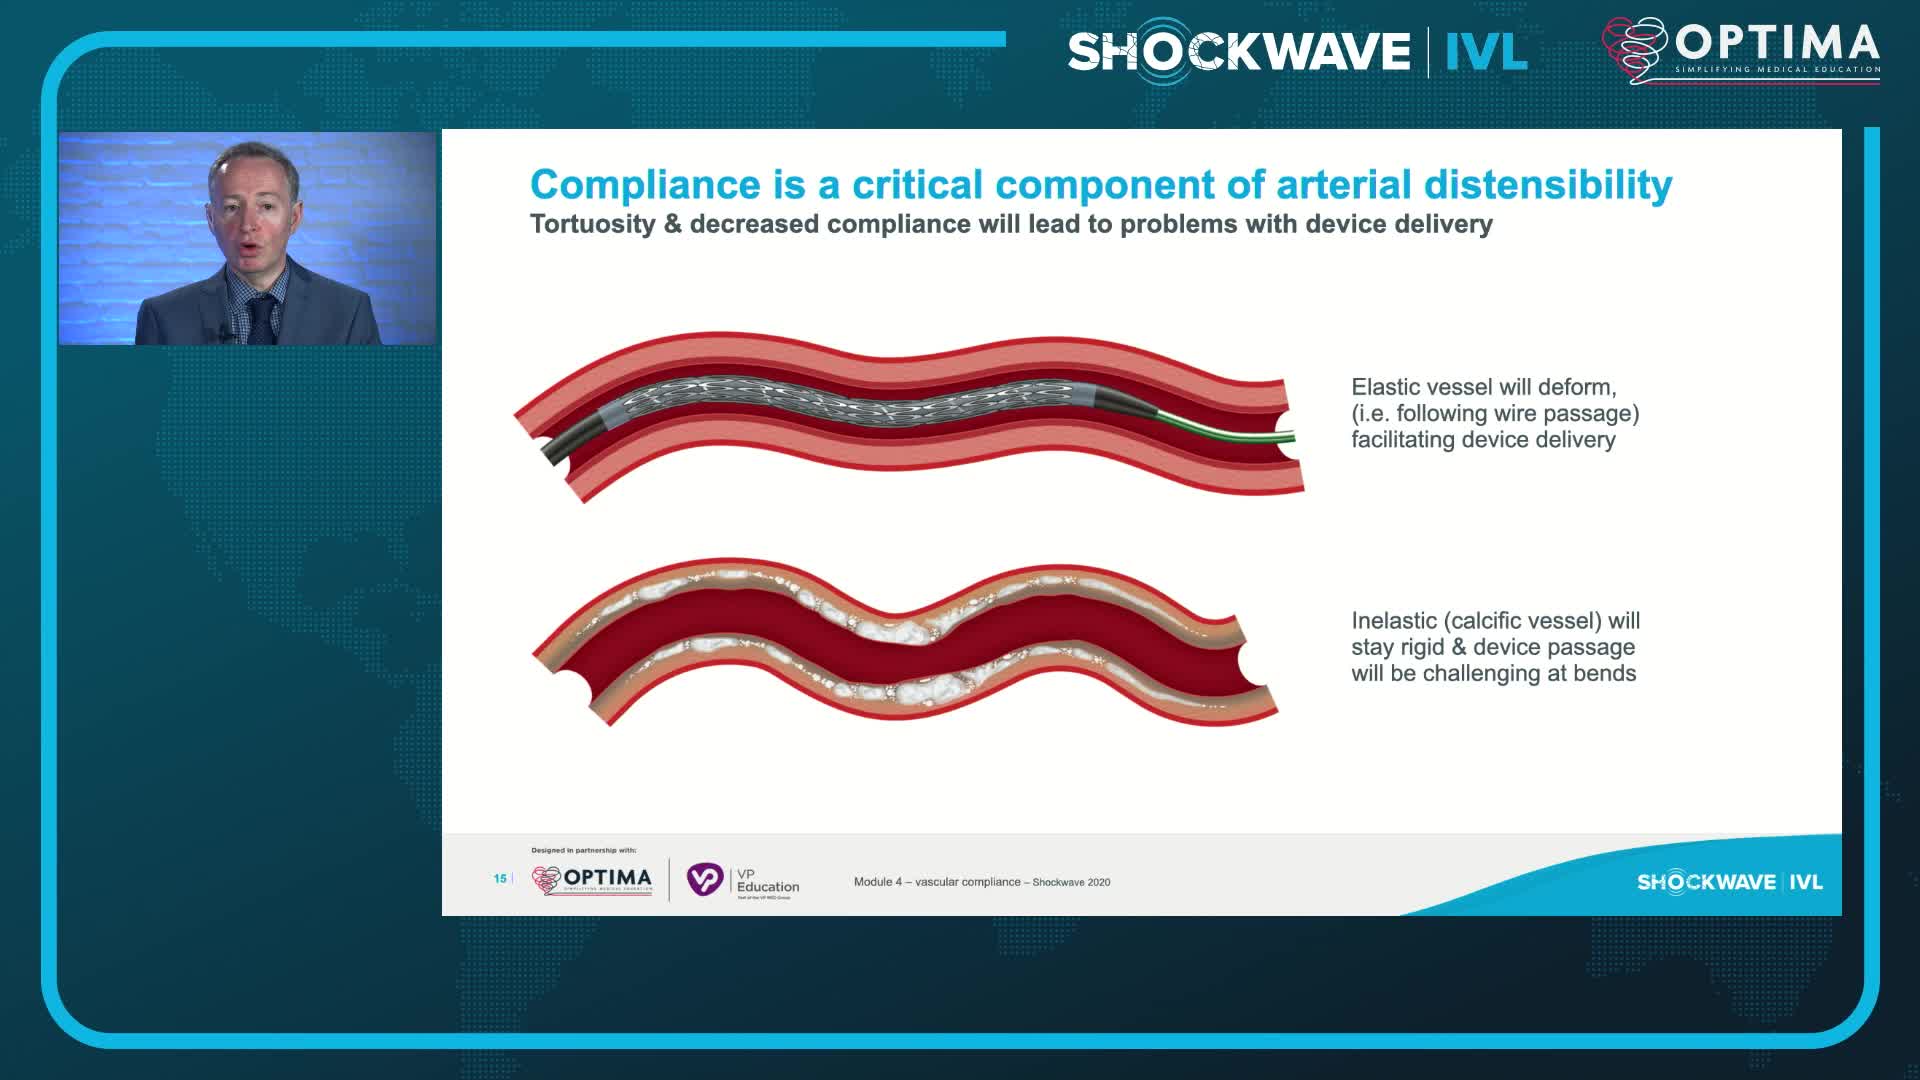

Calcium Masterclass with Shockwave IVL

Treatment of coronary arterial calcium (CAC) has being redefined. We explore the interaction between CAC and patient...